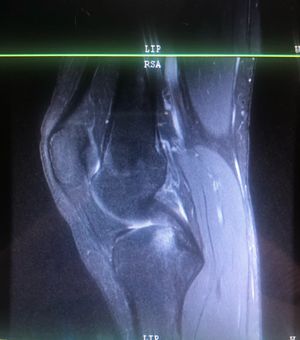

MRI Left Knee

I'm trying to study, but I suck at reading MRIs. It looks like there's a bone bruise but I can't tell if something else is there.

Abnormality seen the knee joint......